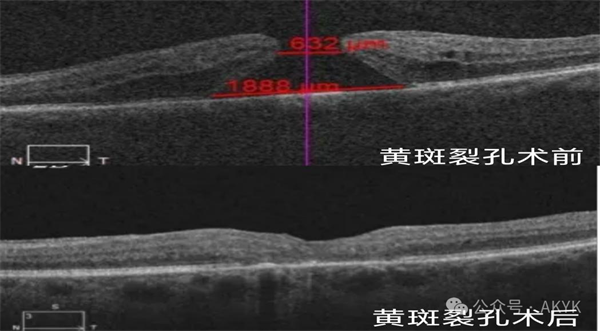

新业务二

复杂黄斑裂孔修复术:修补裂孔提升视力,降低致盲率。